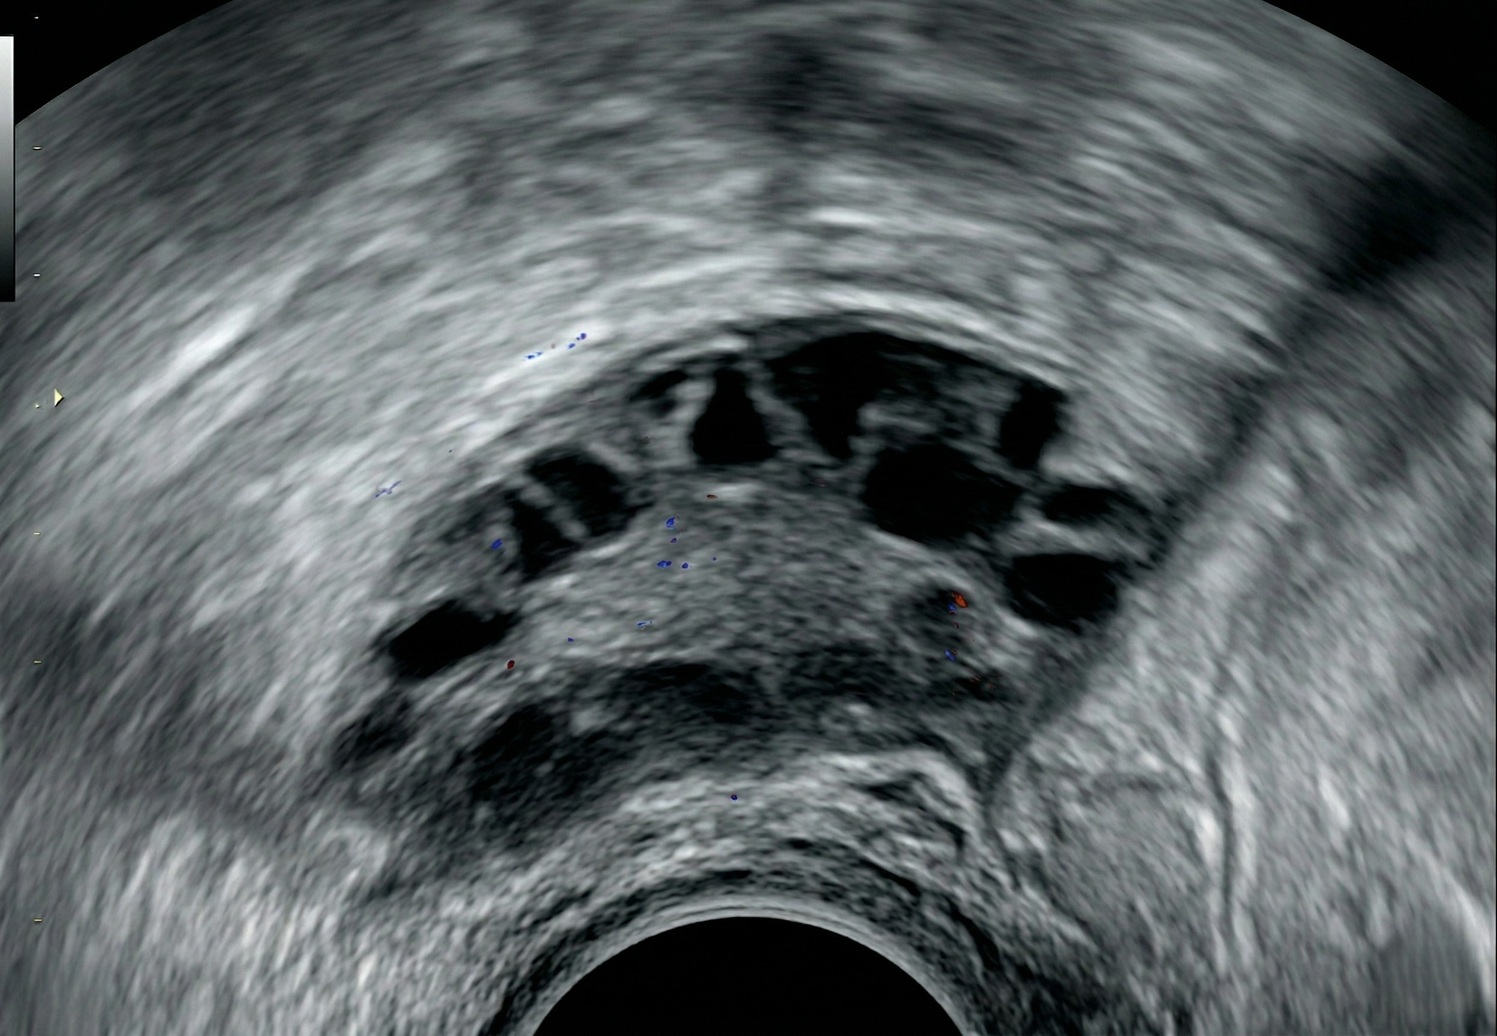

Om PCOS nauwkeurig te diagnosticeren, bekijkt je arts eerst je medische geschiedenis en symptomen. Vervolgens worden diverse onderzoeken en tests uitgevoerd om de diagnose te bevestigen. De diagnostische criteria voor PCOS omvatten onregelmatige menstruaties of zeldzame periodes, verhoogde androgeen niveaus in het bloed en/ of cysten op de eierstokken die zichtbaar zijn via echografie. Voor de diagnose PCOS moet je 3 van de genoemde symptomen hebben.

Ter bevestiging van de diagnose krijg je verschillende medische onderzoeken en tests, zoals een bloedonderzoek. Hierbij wordt er gecontroleerd of er verhoogde niveaus van mannelijke hormonen aanwezig zijn. Daarnaast onderzoeken ze de waarden van LH- en FSH-hormonen, die betrokken zijn bij de ovulatie. In sommige gevallen bekijkt de arts ook cholesterol- en bloedsuikerwaarden om vast te stellen of er sprake is van insulineresistentie. Ten slotte wordt er een (inwendige) echo uitgevoerd om na te gaan of er cysten op de eierstokken aanwezig zijn.